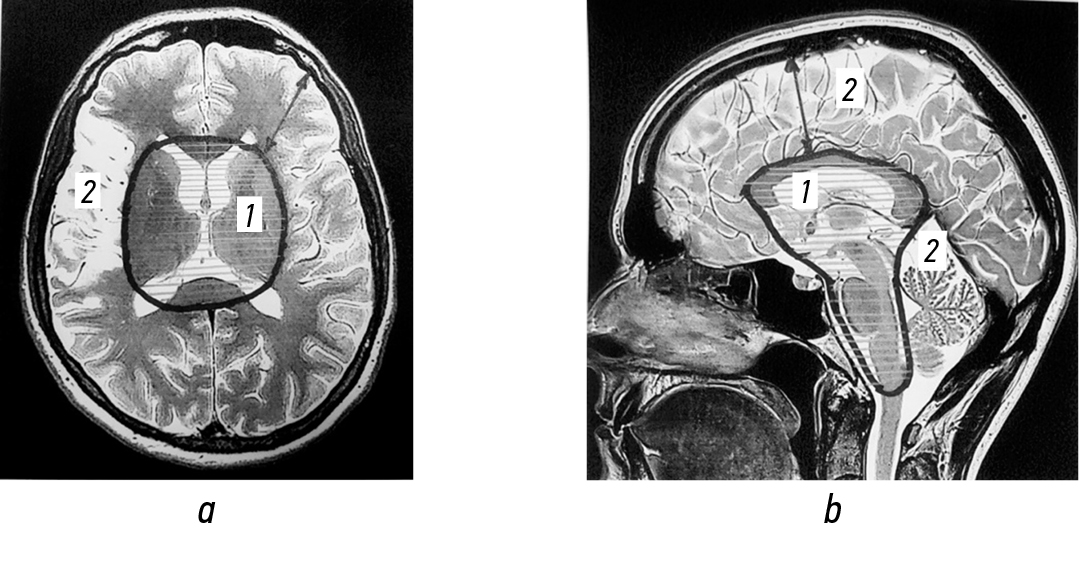

С опорой на данные табл. 4, структуры ГМ (по данным магнитно-резонансной томографии) были условно разделены на две анатомические зоны (рис. 1).

Рис. 1. Условное разделение головного мозга на зоны: a — сагиттальный срез; b — аксиальный срез. 1 — подкорковые образования, желудочки и ствол головного мозга; 2 — кора головного мозга и полушария мозжечка.